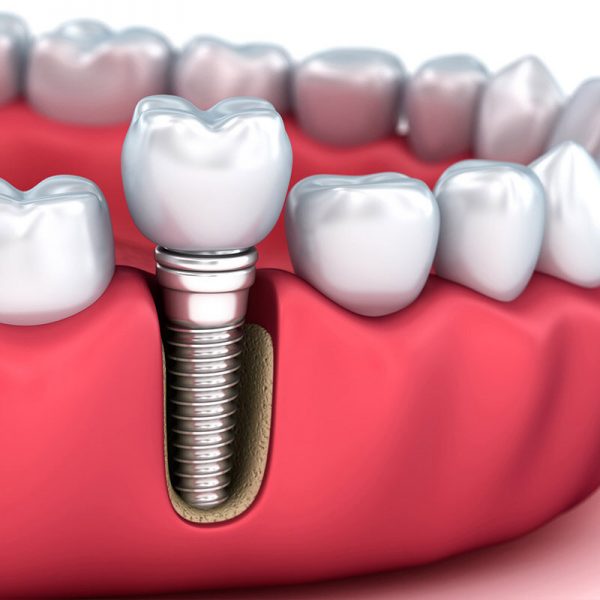

ب- ایمپلنت یا کاشت دندان

ایمپلنت علم جدیدی است که برای باز گرداندن دندانهای از دست رفته با ساخت پایه هایی برای گیر و نصب پروتز متحرک،پیچهایی ازجنس فلزتیتانیوم در داخل استخوان فک با عمل جراحی گذاشته می شود که استحکام یک دندان طبیعی را خواهد داشت. پس از قالب گیری، ساخت پروتز در لابراتوار انجام می گیرد.